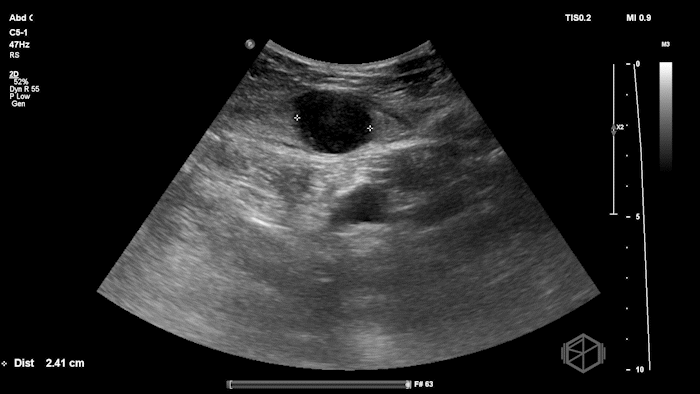

Given the patient’s focal abdominal wall tenderness, a POCUS exam of the left lower quadrant at the point of maximal pain was performed.

She obtained the following images:

The POCUS shows an hypoechoic circular mass within the rectus muscle. There is no active color doppler flow suggesting likely no active bleeding.

Diagnosis: Rectus sheath hematoma (RSH)